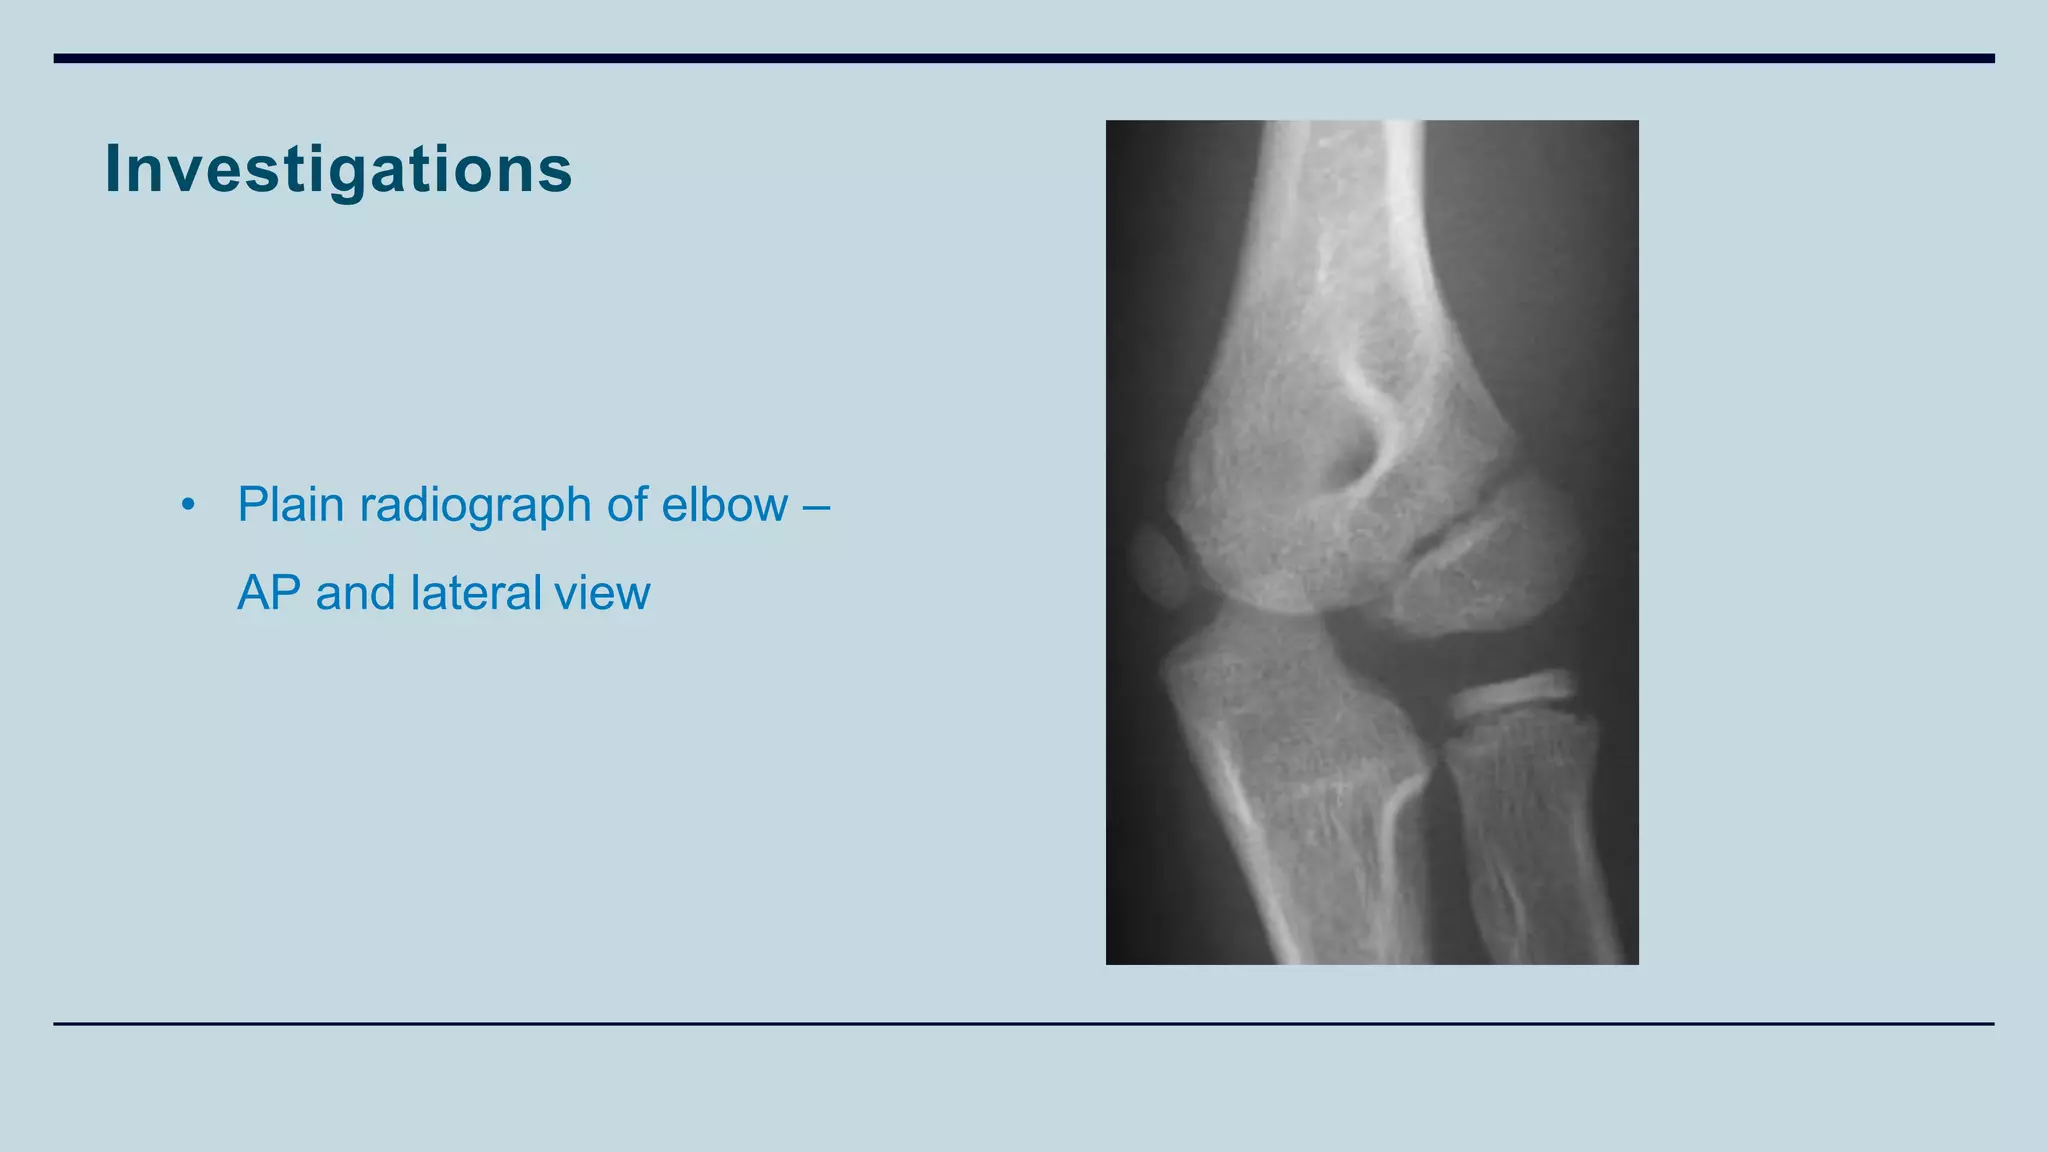

Investigations

• Plain radiograph of elbow –

AP and lateral view

Treatment

• Cast immobilisation for undisplayed fractures

• Open reduction and internal fixation for displaced fractures